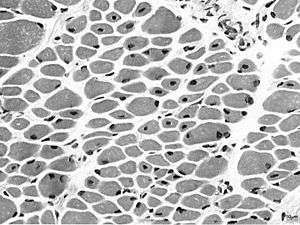

Muscle biopsy from the quadriceps taken at 3 months of age from a girl with X-linked centronuclear ("myotubular") myopathy due to a mutation in the myotubularin (MTM1) gene and extremely skewed X-inactivation (H&E stain, transverse section). Note marked variability in fibre size, moderate increase in connective tissue and numerous central nuclei. | |

On examination of muscle biopsy material, the nuclear material is located predominantly in the center of the muscle cells, and is described as having any "myotubular" or "centronuclear" appearance. In terms of describing the muscle biopsy itself, "myotubular" or "centronuclear” are almost synonymous, and both terms point to the similar cellular-appearance among MTM and CNM. Thus, pathologists and treating physicians use those terms almost interchangeably, although researchers and clinicians are increasingly distinguishing between those phrases.

In general, a clinical myopathy and a muscle biopsy showing a centronuclear (nucleus in the center of the muscle cell) appearance would indicate a centronuclear myopathy (CNM). The most commonly diagnosed CNM is myotubular myopathy (MTM). However, muscle biopsy analysis alone cannot reliably distinguish myotubular myopathy from other forms of centronuclear myopathies, and thus genetic testing is required.